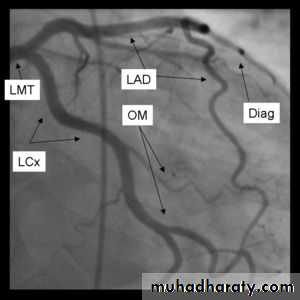

Angiography of coronary vessels